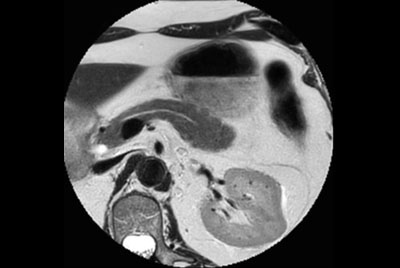

Pancreas nodule – Free breathing